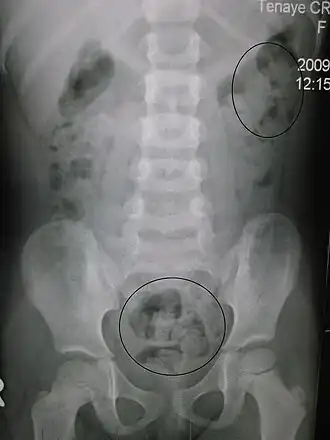

Raio-x de obstipação numa criança. Os círculos assinalam os locais opacos de aglomeração de fezes.